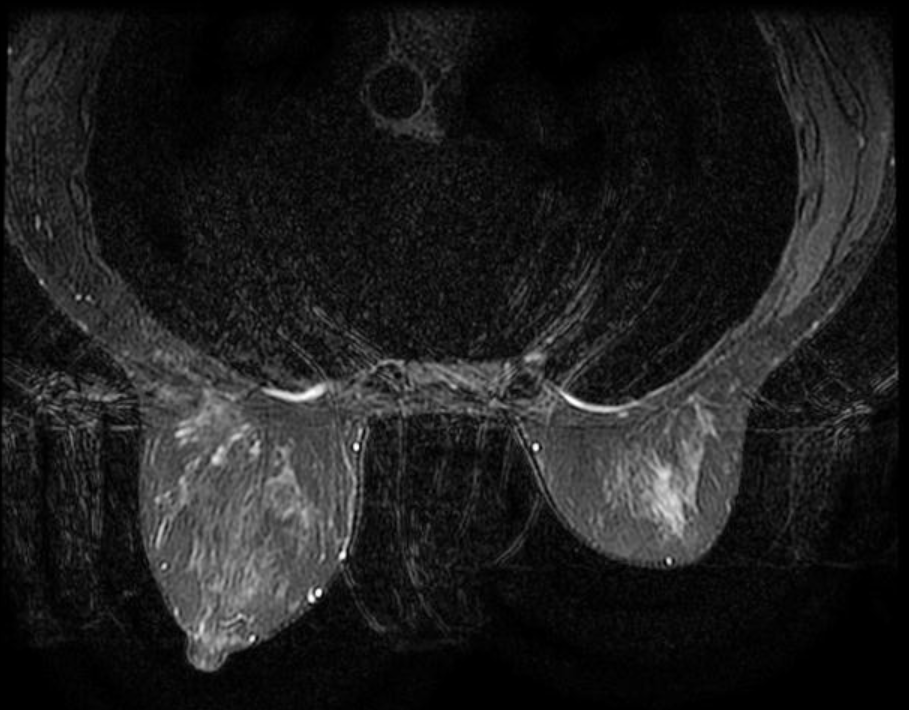

- Là phương tiện hình ảnh tốt nhất trong đánh giá biến chứng rách vỡ túi ngực.

2.6 Đánh giá túi ngực

Cộng hưởng từ vú là phương tiện tốt nhất để xác định có rách vỡ túi ngực hay không.